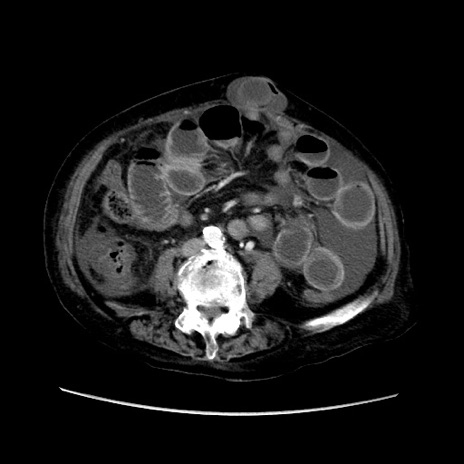

症例31(横断像)

【症例】80歳代 女性

【主訴】腹部膨満感

【現病歴】他院にて肝硬変にてフォロー中。1週間前から便秘、腹部膨満感、臍部腫瘤あり受診となる。

【既往歴】肝硬変

【身体所見】腹部膨隆あり、皮膚変化なし、疼痛なし。

【データ】WBC 4600、CRP 0.25